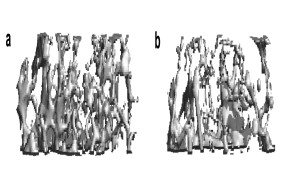

Cellular and molecular basis of osteoporosis

Bone loss (osteoporosis) is the most common bone disease in humans. Although the disease is asymptomatic for a long time, in its advanced stages it results in reduced bone mass and quality and a greatly increased risk of fractures. This disease is triggered by an imbalance in the activity of bone cells, the bone-forming osteoblasts and the bone-resorbing osteoclasts. In our research, we investigate the regulation of these cells with the aim of identifying novel factors that counteract bone resorption and promote the formation of new bone.

Fig.: Radiological imaging (µCT) of altered bone structure in systemic bone loss disorders. (a) Normal trabecular bone architecture. (b) Rarified and thinned trabecular structure in post-menopausal osteoporosis.